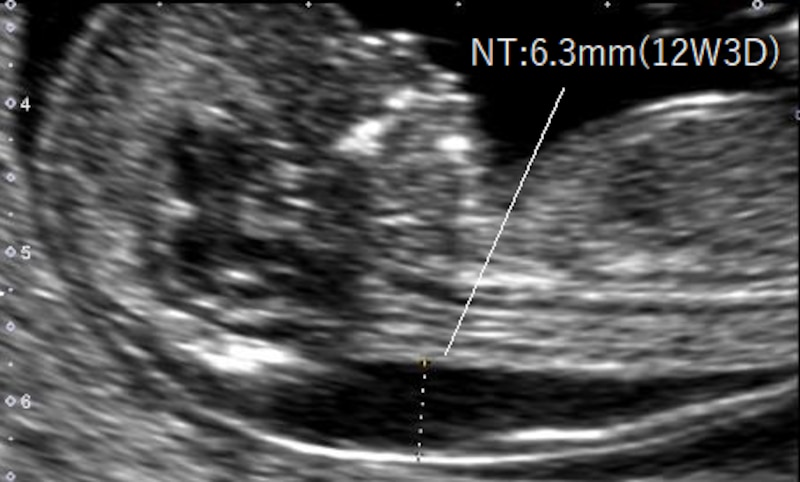

NT(nuchal translucency)とは、妊娠初期の超音波検査で見える、胎児の首の後ろのむくみ(浮腫)のことです。超音波は水が溜まった部分は反射しないので、黒く抜けてみえます。医学用語では後頚部透亮像(後頚部:nuchal、透亮像:translucency)といいます。NT計測の規約に従って画像を拡大すると、浮腫の厚さに違いはありますが、全ての胎児に見つかります。この時期、胎児の心臓や大きな血管は、ほぼ形成されていますが、全身の血管やリンパ管の循環網は未発達で、血液や体液の還流がうっ滞しやすいために、生理的にむくみを生じます。

特に染色体異常や心臓血管系異常があると、循環とのアンバランスは起こりやすく、NTが厚いほど、胎児の染色体異常や胎児疾患の可能性は高まり、出生前診断の参考指標の一つになります。

NT値の計測には、厳密な規約があります。

- 妊娠11週0日~妊娠13週6日の間で計測する

- 胎児CRL(頭殿長)が45㎜~84㎜

- 胎児の頭部・胸部を画面いっぱいに拡大する

妊娠週数には少なくとも3日程度の誤差はあります。そのため、妊娠11週0日~13週6日の間でも、 CRLが45㎜未満、または84㎜を超えていると、NT値による診断はできません。 そこで、NTを活用した出生前診断には、妊娠12週頃の検査が勧められます。